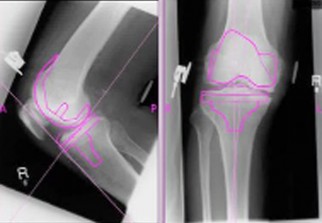

La spécialiste a indiqué en marge du 13e congrès de la Société algérienne  de rhumatologie, que 23 pc des femmes de plus de 50 ans sont atteintes de  gonarthrose (arthrose du genou) et 26 % d'entre elles souffrent de  rhizarthrose (arthrose des doigts). Elle a appelé à une bonne prise en  charge de cette maladie avant qu'elle ne devienne invalidante, et à son  inclusion dans la liste des maladies indemnisées par la sécurité sociale.

Il a appelé au dépistage de l'arthrose, qualifiée de "maladie insidieuse",  qui n'apparait qu'après détérioration de l'os, ce qui influe négativement  sur la vie des patients.